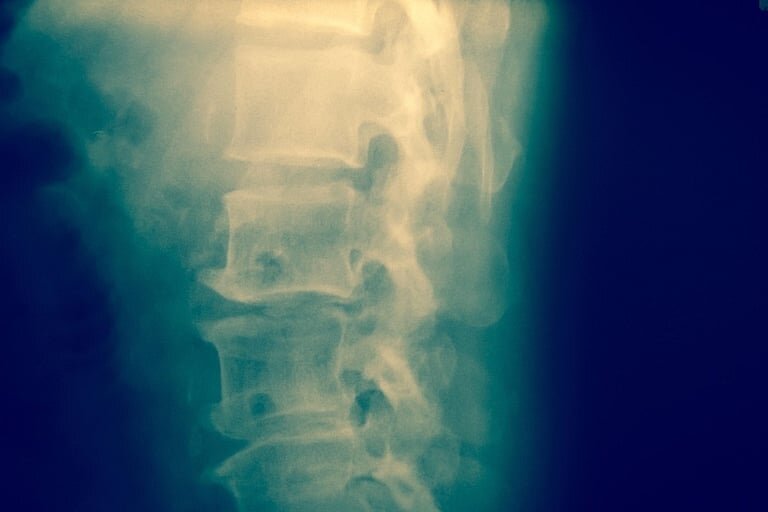

Un nuevo decodificador de ondas cerebrales ha mostrado resultados prometedores al utilizar estimulación eléctrica en la médula espinal para provocar el movimiento de las piernas, según un grupo de investigadores.

Este avance podría, en el futuro, contribuir a recuperar la movilidad en personas con lesiones medulares.

En pruebas realizadas con 17 voluntarios sin daño en la médula espinal, el dispositivo logró inducir el movimiento de las extremidades inferiores mediante estimulación espinal, de acuerdo con un estudio publicado en la revista Journal of NeuroEngineering and Rehabilitation.

Este experimento representa un paso inicial hacia el desarrollo de una interfaz que conecte directamente el cerebro con la médula espinal, usando en tiempo real las ondas cerebrales y la estimulación espinal para permitir el movimiento en personas con parálisis por lesión medular.